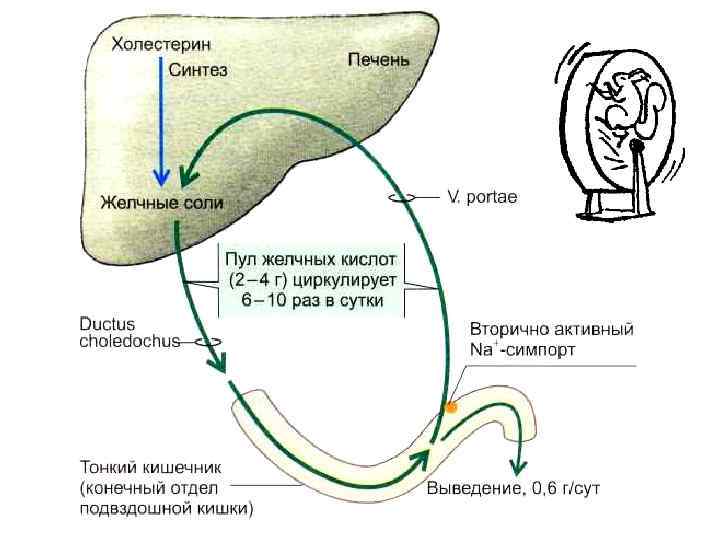

Кишечно-печеночная циркуляция желчных солей • Сколько раз за день пул желчных солей (ЖС) циркулирует между кишечником и печенью, зависит от содержания жира в пище. • При нормальной пище пул ЖС циркулирует 2 раза в день, • При богатой жирами пище - 5 раз и больше • На рисунке дано приблизительное представление

Кишечно-печеночная циркуляция желчных солей • Сколько раз за день пул желчных солей (ЖС) циркулирует между кишечником и печенью, зависит от содержания жира в пище. • При нормальной пище пул ЖС циркулирует 2 раза в день, • При богатой жирами пище - 5 раз и больше • На рисунке дано приблизительное представление

Кишечно-печеночная циркуляция желчных солей

Кишечно-печеночная циркуляция желчных солей

Кишечно-печеночная циркуляция желчных солей

Кишечно-печеночная циркуляция желчных солей

• Кишечно-печеночная циркуляция веществ (схема). • Харкевич

• Кишечно-печеночная циркуляция веществ (схема). • Харкевич